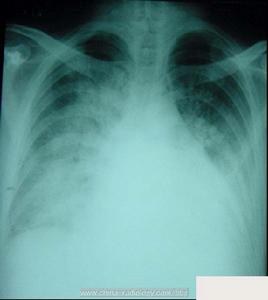

左心衰 x線表現(三)早期X線檢查

肺靜脈充盈期左側心力衰竭在X線檢查時僅見肺上葉靜脈擴張、下葉靜脈較細,肺門血管陰影清晰。在肺間質水腫期可見肺門血管影增粗、模糊不清,肺血管分支擴張增粗,或肺葉間淋巴管擴張。在肺泡水腫階段,開始可見密度增高的粟粒狀陰影,繼而發展為雲霧狀陰影。急性肺水腫時可見自肺門伸向肺野中部及周圍的扇形雲霧狀陰影。此外,左側心力衰竭有時還可見到局限性肺葉間、單側或雙側胸水;慢性左側心力衰竭患者還可有葉間胸膜增厚,心影可增大(左心室增大)。